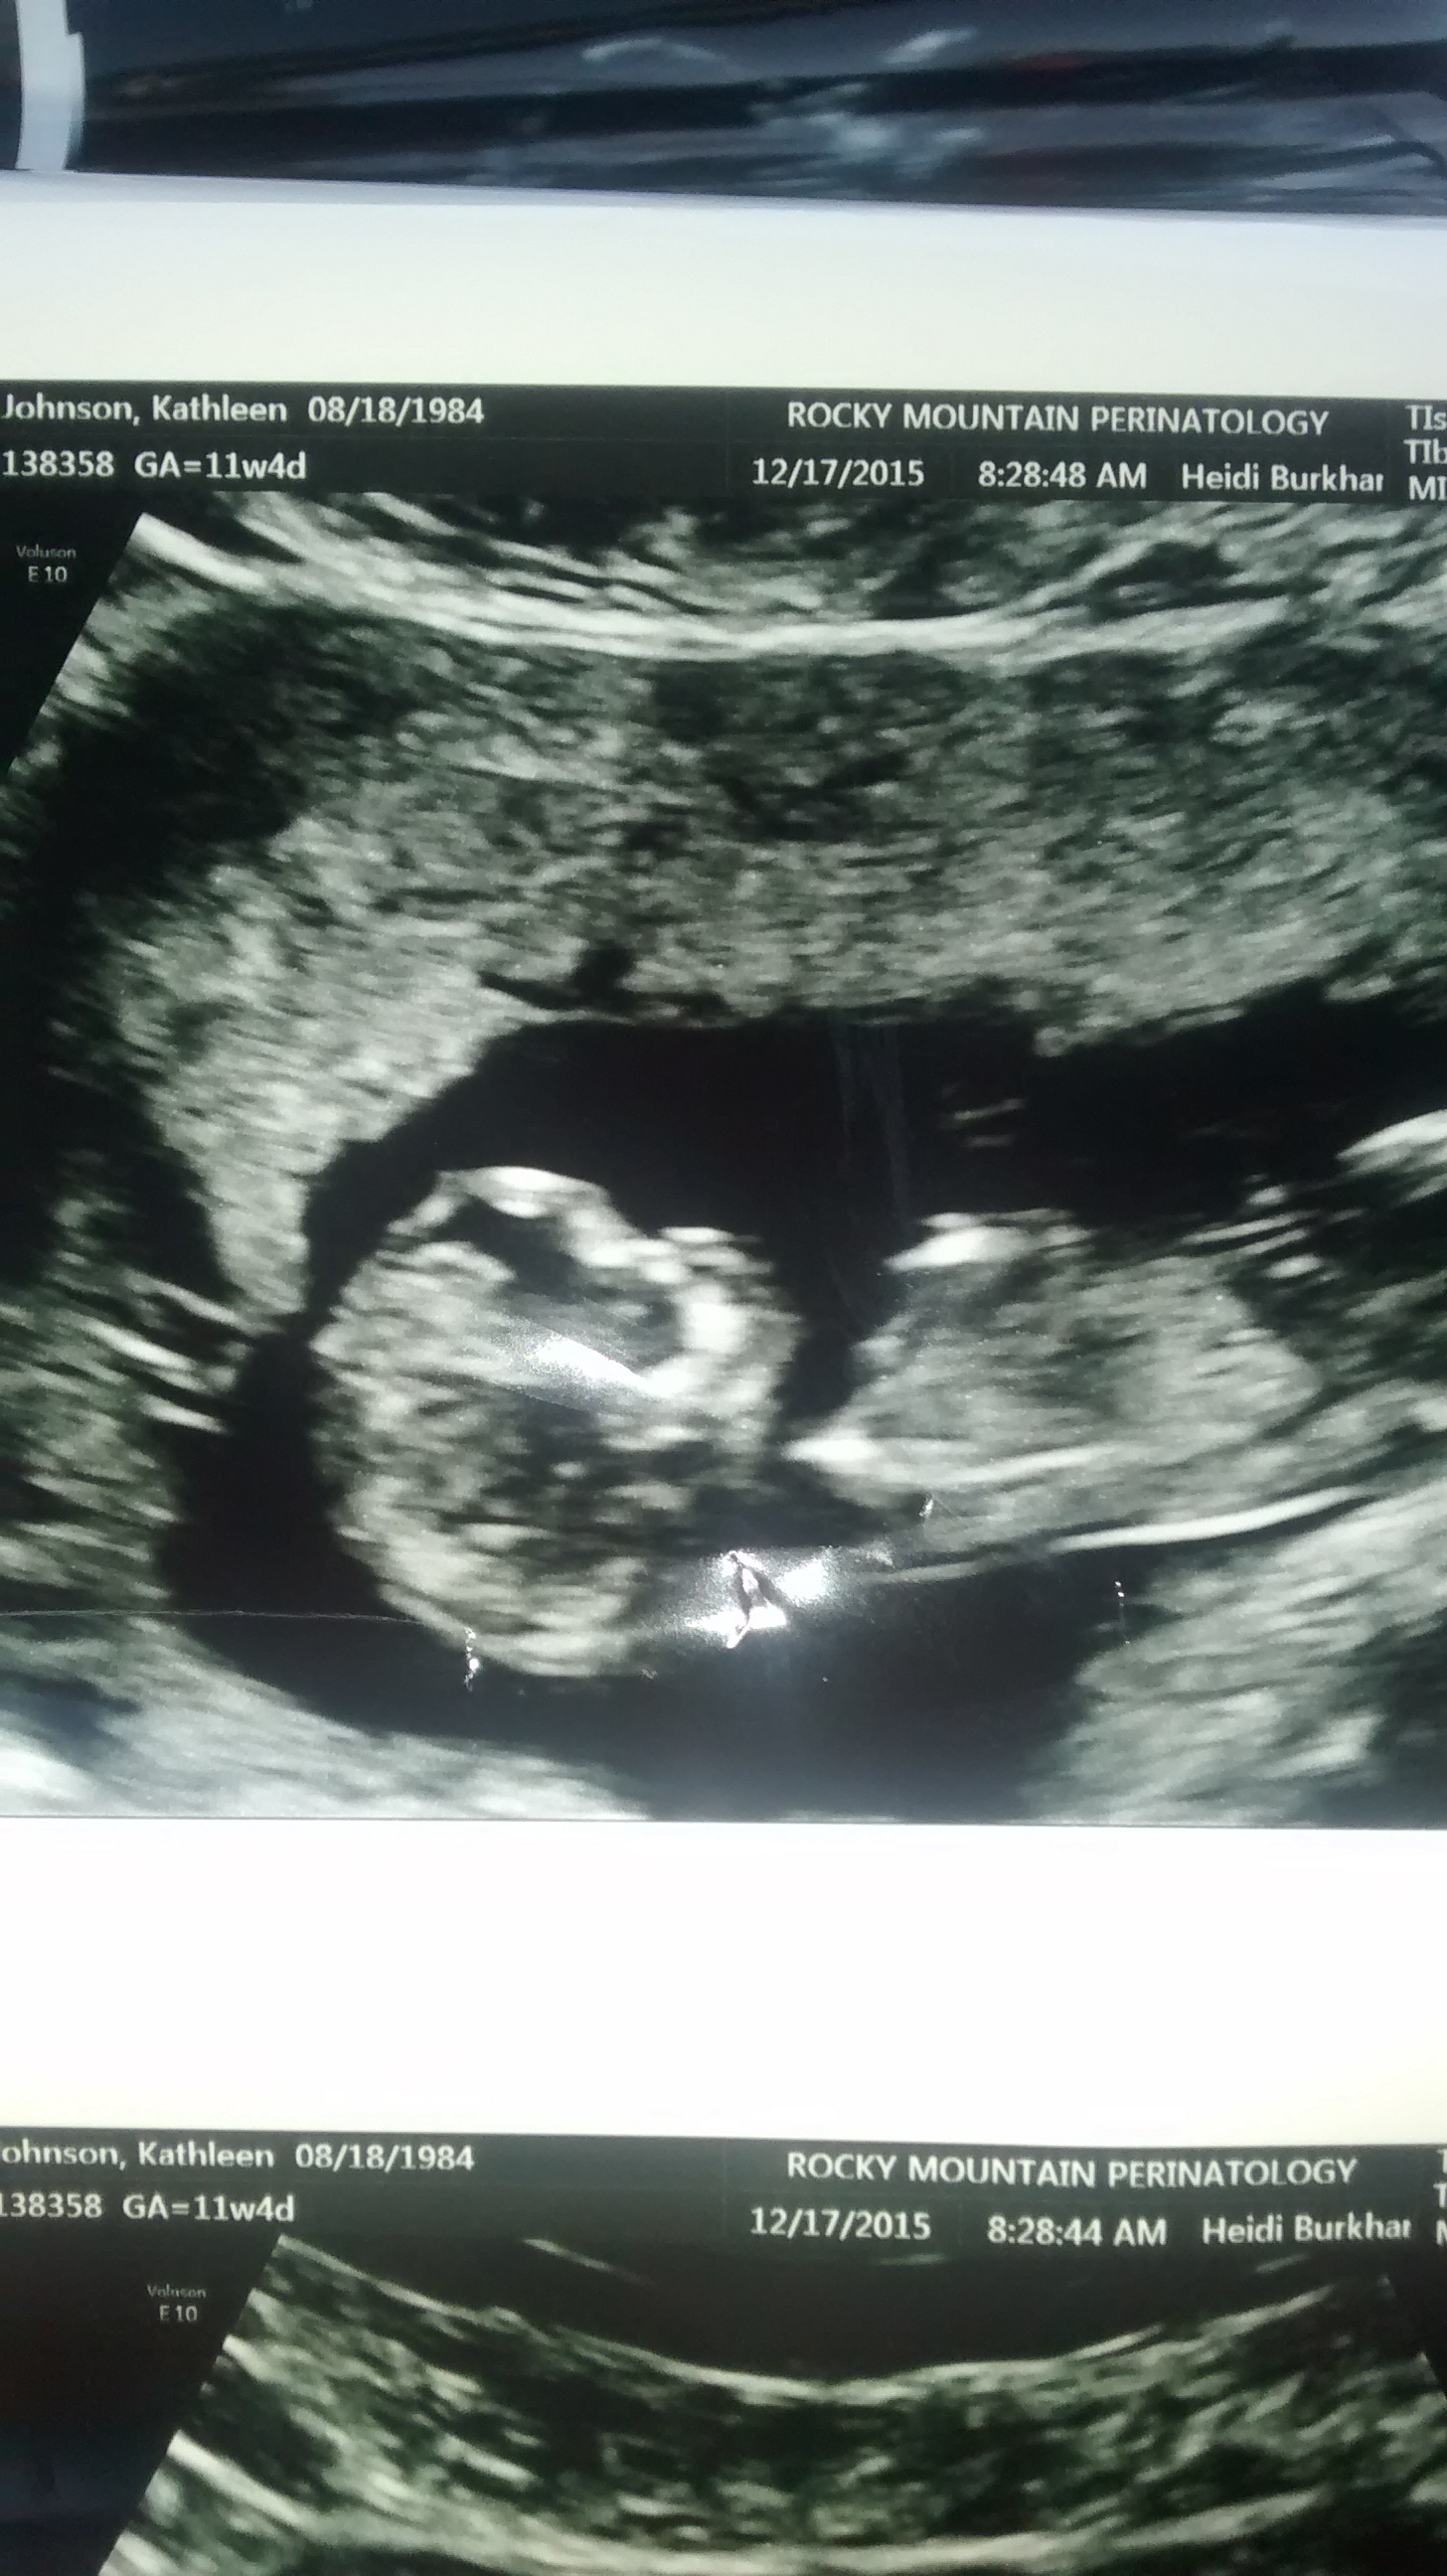

11 weeks 4 days is way too early to guess but a wild guess( skull theory girl :) Sent from my GT-I9305T using Tapatalk

Skull looks girly.